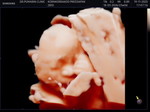

ปากมกลูกเปิด2เซน!!!!!

เมื่อวานมีมูกเลือดออก แต่ไม่ปวดท้องไม่มีอาการอะไร ปากมดลูกเปิด2เซนหมอไม่เร่งไห้กับบ้านแล้ว ตอนนี้มูกก็ยังออกอยู่ค่ะทำไงดีค่ะ!!บอกทีน้ะค่ะ